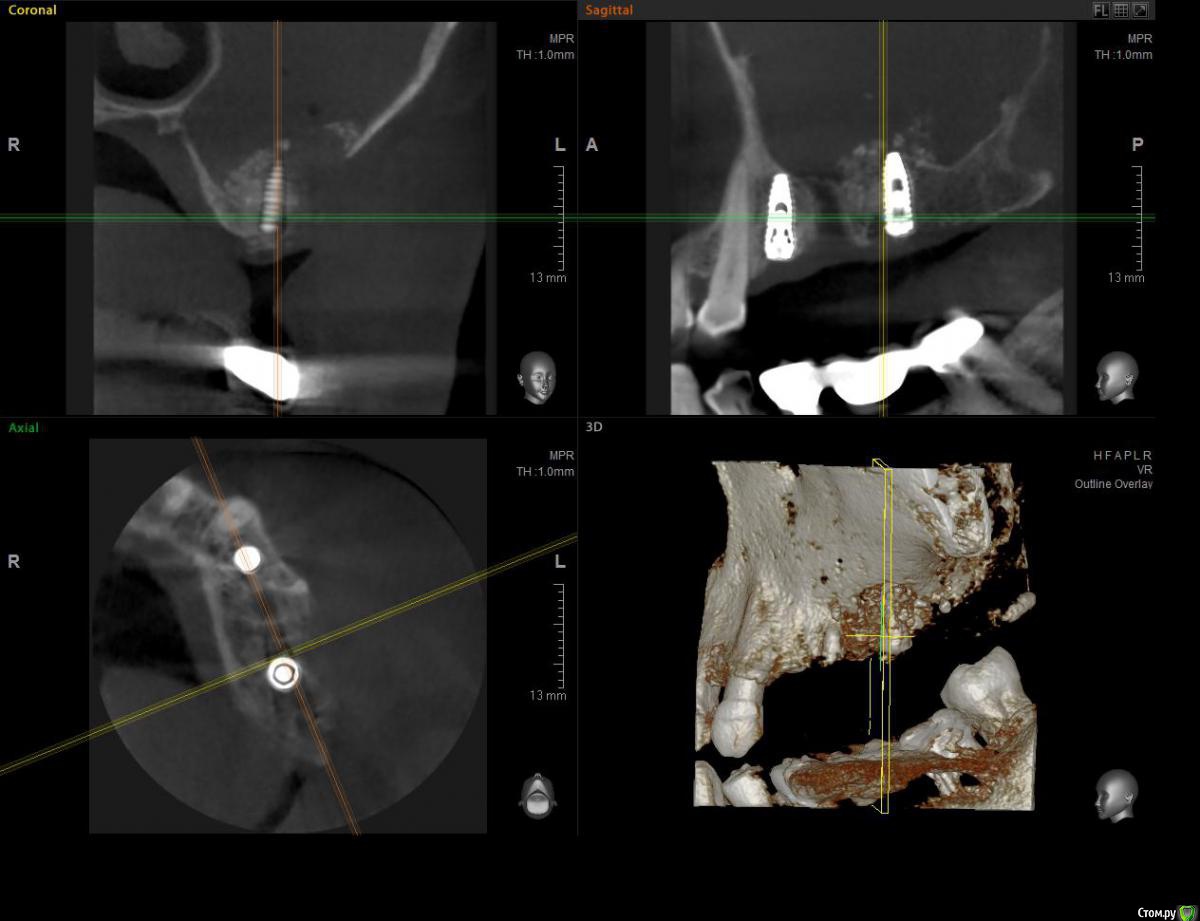

ossa-rr Опубликовано 12 июня, 2017 Поделиться Опубликовано 12 июня, 2017 (изменено) Коллеги, прошу помощи! В конце апреля установил два импланта 24 и 26. В области 26 с открытым синусом. Операция без осложнений, без перфорации и пр. Снял швы через 10 дней. Через месяц пациентка позвонила, сказала, что припухла. Явилась с клиникой периостита в области окна. Вскрыл , установил дренаж на сутки. Есть ли надежда или открывать и убирать все? И еще вопрос по перфорации на кт - как считаете, могла ли она возникнуть как следствие гнойного расплавления или все-таки непосредственно при синус - лифте?Скрины повторного кт : Изменено 12 июня, 2017 пользователем ossa-rr Ссылка на комментарий

kamranchick Опубликовано 12 июня, 2017 Поделиться Опубликовано 12 июня, 2017 Коллеги, прошу помощи! В конце апреля установил два импланта 24 и 26. В области 26 с открытым синусом. Операция без осложнений, без перфорации и пр. Снял швы через 10 дней. Через месяц пациентка позвонила, сказала, что припухла. Явилась с клиникой периостита в области окна. Вскрыл , установил дренаж на сутки. Есть ли надежда или открывать и убирать все? И еще вопрос по перфорации на кт - как считаете, могла ли она возникнуть как следствие гнойного расплавления или все-таки непосредственно при синус - лифте?Скрины повторного кт :походу перфорация есть, понаблюдайте, думаю весь графт может инфицироваться тут и нужны снимки до Ссылка на комментарий

ПалСаныч Опубликовано 13 июня, 2017 Автор Поделиться Опубликовано 13 июня, 2017 по моему мнению перфорация есть, ибо графт разлетелся по пазухе. Думаю нужно все убрать из места подсадки, пазуху пропунктировать пару раз у ЛОРа, антибиотики, сосудосуживающие. И через месяца 2 контроль КЛТ. Ссылка на комментарий